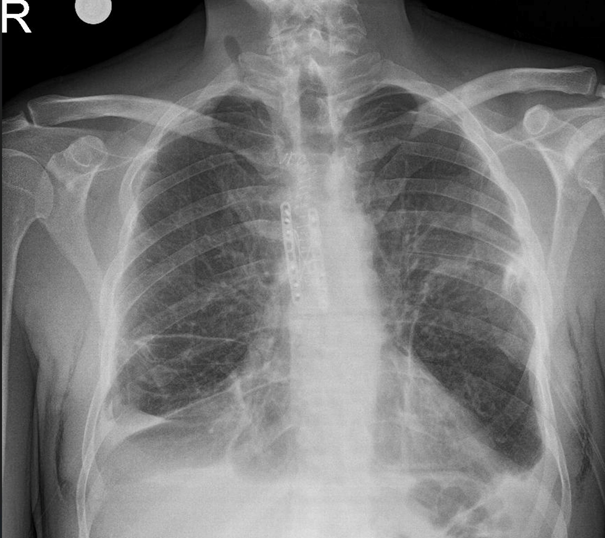

Based on these findings, the patient was taken to surgery after obtaining informed consent and completing preoperative preparation. An anterior approach was used to expose the sternal fracture line intraoperatively. The fracture ends were mobilized, anatomically reduced, and stabilized using a titanium plate (Figure 3). Postoperative chest radiographs confirmed appropriate alignment and stabilization of the sternum (Figure 4). The patient was closely monitored postoperatively; no complications were observed, and he was discharged within the expected recovery period.

Figure 4 Postoperative chest radiograph of the patient.